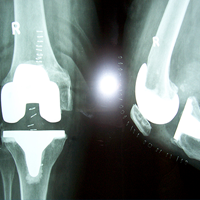

Case:1 TKR

Post-Surgery

Case:2 TKR

Post-Op